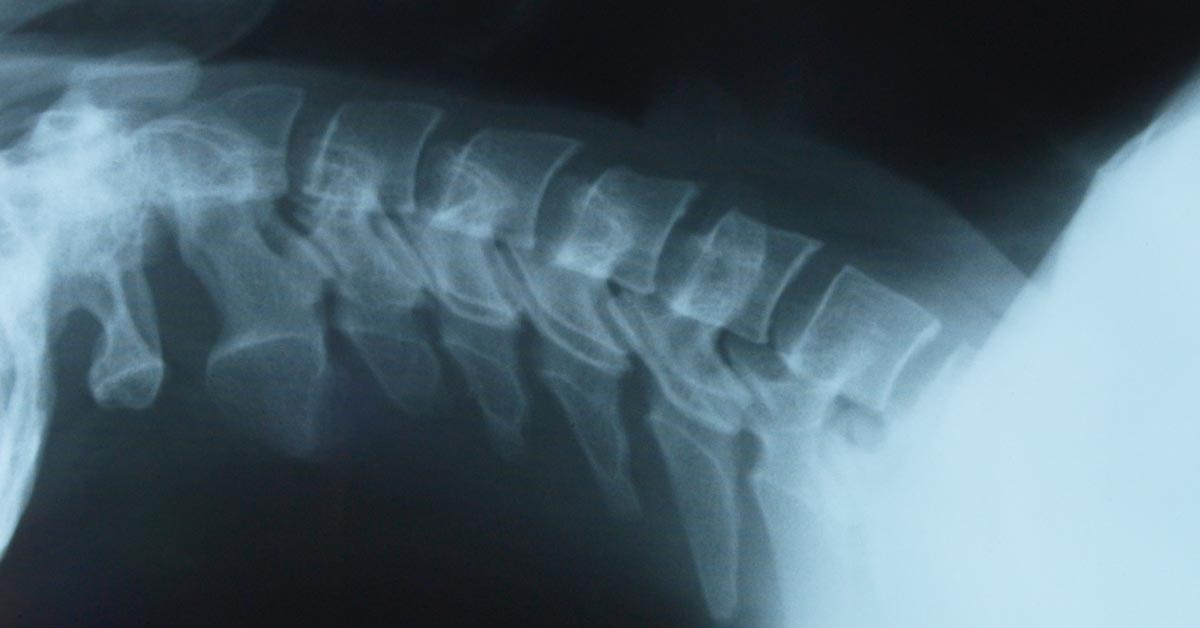

Prevent Back Surgery with Chiropractic

Downtown St. Louis, MO Back Pain Treatment without SurgeryEvery year, over 500,000 people have back surgery in the US. Although sometimes it's necessary to have back surgery, the reality is that if you can prevent this type of invasive procedure, you're often better off.